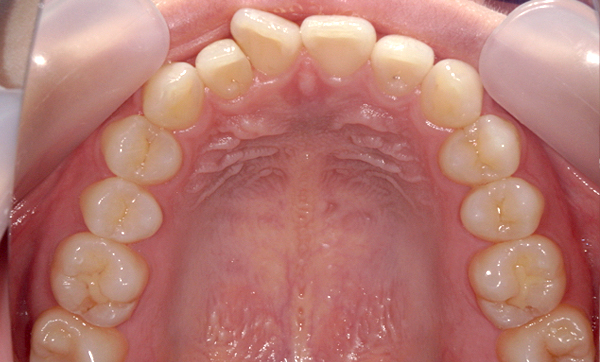

症例_009 「上下の前歯」症例

治療期間:7ヶ月金額:54万円+税20代女性捻転歯一部の反対咬合前歯のガタガタ